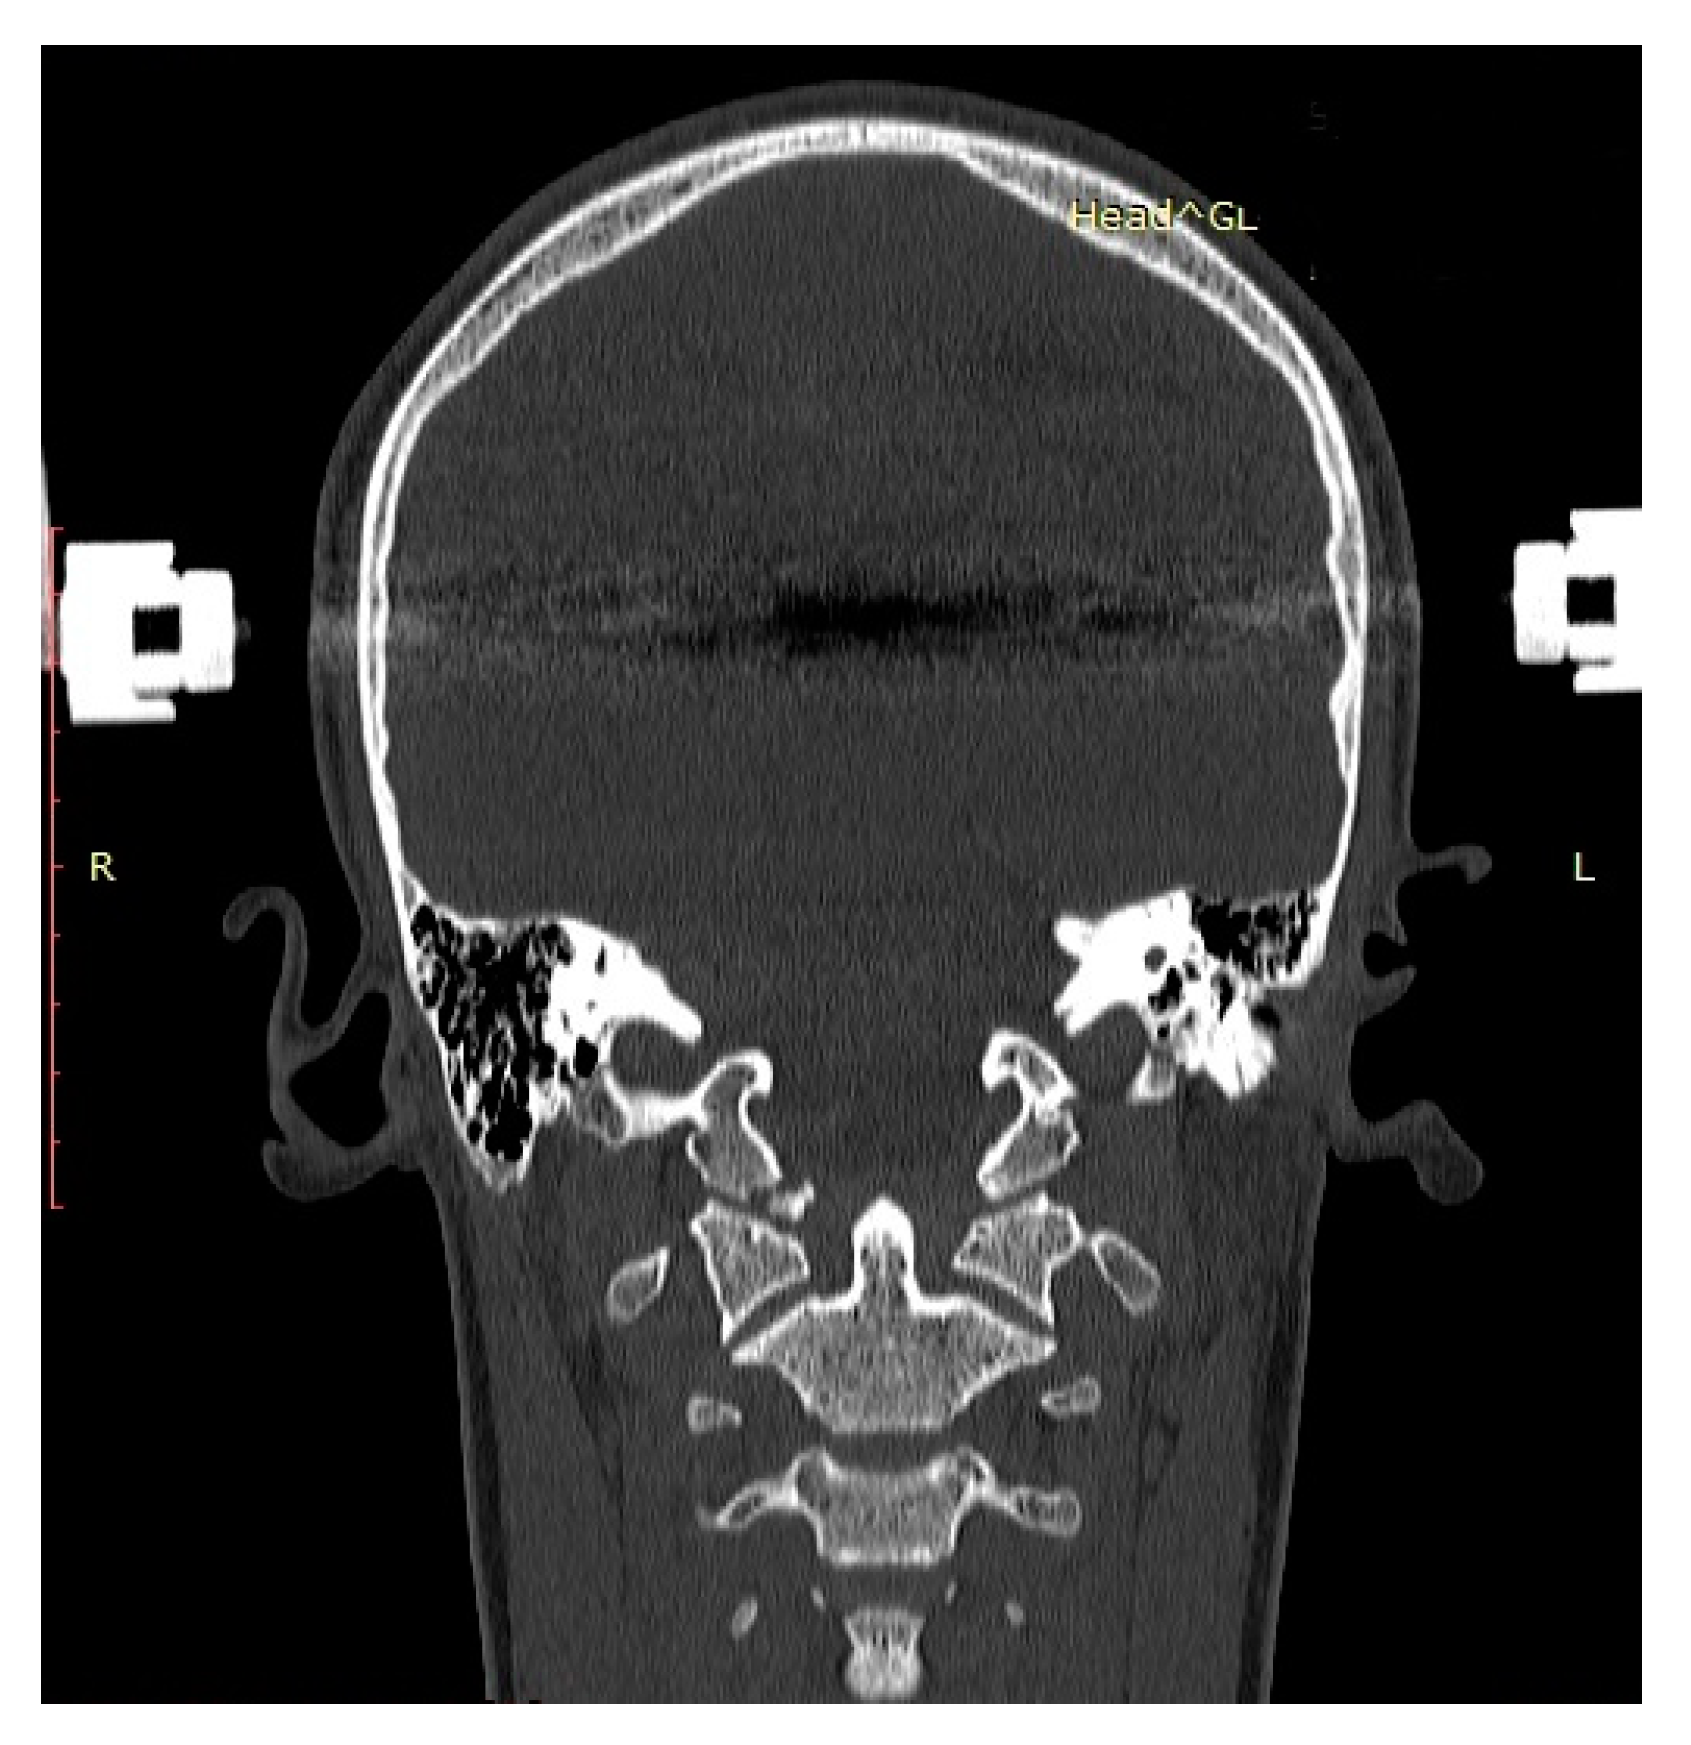

| P.P. | M | 15.2 | III (unstable) | IIB | Road traffic accident (car passenger) | Fracture frontal bone, fracture frontal sinus, contusion of frontal lobe | Halo-vest immobilization: 12.5 weeks |

| K.D. | F | 15 | III (unstable) | IIB | Pedestrian hit by car | Lung contusion, brain concussion, multiple abrasions | Halo-vest immobilization: 13 weeks |

| R.M. | F | 18 | I (unstable) | IIB | Road traffic accident (car passenger) | Pneumothorax, neurogenic vocal cord injury, post-traumatic aphasia | Halo-vest immobilization: 14 weeks |

| S.D. | M | 14.7 | III (stable) | IIA | Road traffic accident (car passenger) | Fracture of frontal bone, fracture of nasal bone, subdural hematoma | Minerva-brace immobilization |

| B.W. | F | 16 | I (stable) | IIA | Fall from a height | Fracture of frontal bone, fracture of nasal bone, subarachnoid hemorrhage, fracture of transverse process Th3-5, fracture of radius | Minerva-brace immobilization |

| M.O. | M | 16.1 | I (stable) | IIA | Bicycle incident | Fracture frontal bone, fracture maxillary sinus, fracture orbit, metacarpal fracture | Minerva-brace immobilization |